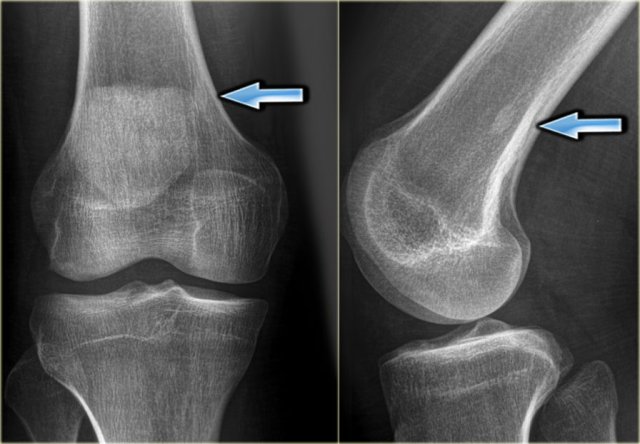

Here the reactive sclerosis is the most obvious finding on the X-ray.

There is reactive sclerosis with a nidus that is barely visible on the radiograph (blue arrow), but clearly visible on the CT (red arrows).

CT scan is usually very helpful in detecting the nidus and differentiating osteoid osteoma from other sclerotic lesions like osteoblastoma, osteomyelitis, arthritis, stress fracture and enostosis.

MRI also may detect the nidus, combined with abundant bone marrow and soft tissue edema.